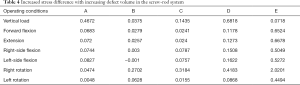

Under each working condition, as the defect volume increased, the stress differences between consecutive groups were as listed in Table 4.

Full table

We used the data to generate a dot plot to more intuitively show the relationship between the defect volume and the increase in stress (Figure 14).

The 5/5 defect in the anterior column of the injured vertebra was a simulated extreme condition that does not exist in actual clinical practice, so we removed this condition from consideration. According to the chart, after the implantation of the internal fixator, the stress increased significantly when the injured vertebra showed a defect. As the defect volume increased, the stress increased correspondingly, and the increase in stress represented by group D (stress difference between the 3/5 defect group and the 4/5 defect group) was the greatest.